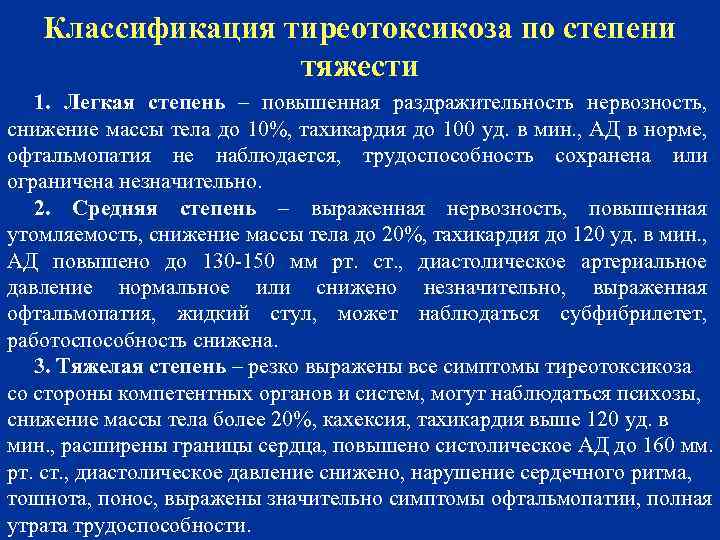

Классификация тиреотоксикоза по степени тяжести 1. Легкая степень – повышенная раздражительность нервозность, снижение массы тела до 10%, тахикардия до 100 уд. в мин. , АД в норме, офтальмопатия не наблюдается, трудоспособность сохранена или ограничена незначительно. 2. Средняя степень – выраженная нервозность, повышенная утомляемость, снижение массы тела до 20%, тахикардия до 120 уд. в мин. , АД повышено до 130 -150 мм рт. ст. , диастолическое артериальное давление нормальное или снижено незначительно, выраженная офтальмопатия, жидкий стул, может наблюдаться субфибрилетет, работоспособность снижена. 3. Тяжелая степень – резко выражены все симптомы тиреотоксикоза со стороны компетентных органов и систем, могут наблюдаться психозы, снижение массы тела более 20%, кахексия, тахикардия выше 120 уд. в мин. , расширены границы сердца, повышено систолическое АД до 160 мм. рт. ст. , диастолическое давление снижено, нарушение сердечного ритма, тошнота, понос, выражены значительно симптомы офтальмопатии, полная утрата трудоспособности.

Классификация тиреотоксикоза по степени тяжести 1. Легкая степень – повышенная раздражительность нервозность, снижение массы тела до 10%, тахикардия до 100 уд. в мин. , АД в норме, офтальмопатия не наблюдается, трудоспособность сохранена или ограничена незначительно. 2. Средняя степень – выраженная нервозность, повышенная утомляемость, снижение массы тела до 20%, тахикардия до 120 уд. в мин. , АД повышено до 130 -150 мм рт. ст. , диастолическое артериальное давление нормальное или снижено незначительно, выраженная офтальмопатия, жидкий стул, может наблюдаться субфибрилетет, работоспособность снижена. 3. Тяжелая степень – резко выражены все симптомы тиреотоксикоза со стороны компетентных органов и систем, могут наблюдаться психозы, снижение массы тела более 20%, кахексия, тахикардия выше 120 уд. в мин. , расширены границы сердца, повышено систолическое АД до 160 мм. рт. ст. , диастолическое давление снижено, нарушение сердечного ритма, тошнота, понос, выражены значительно симптомы офтальмопатии, полная утрата трудоспособности.